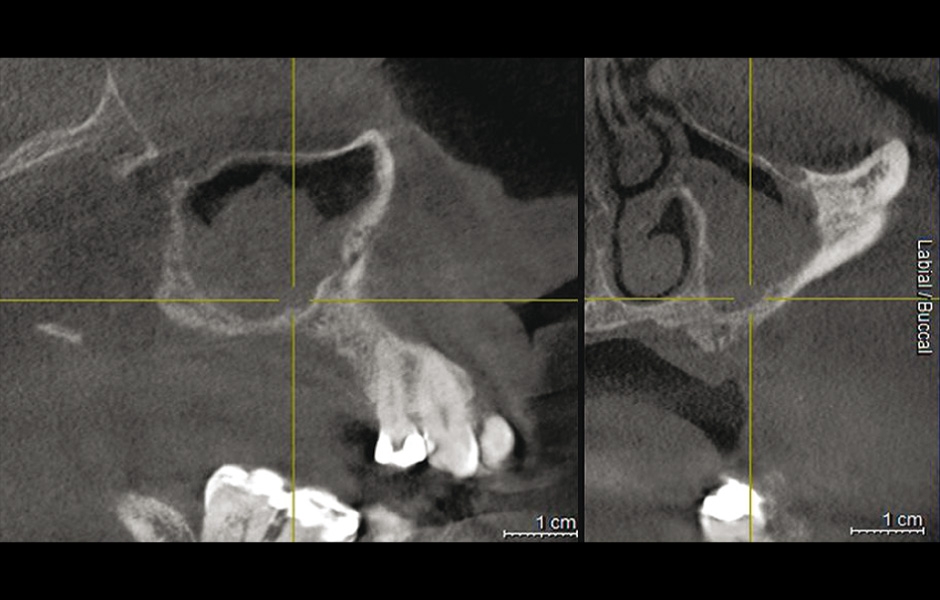

Obr. 7: CBCT: částečné zastínění pravého maxilárního sinu po neúspěšném sinus liftu s bovinním kostním náhradním materiálem.

Do studie bylo zařazeno 10 pacientů s aspergilózou maxilárního sinu. U všech pacientů byl na panoramatických snímcích i na CBCT patrný radiopakní stín. CBCT navíc ukázalo, že čelistní dutina byla kompletně vyplněna homogenní patologickou masou. Chirurgická léčba sinu byla provedena za antibiotické profylaxe (Amoxicillin 2 g/den po dobu 7 dní) a intravenózní sedace (Midazolam). Kostní okénko bylo vytvořeno mikropilkou (DENTSPLY Implants), umožnilo bezpečný přístup do sinu. Po odklopení separovaného kostního fragmentu byla aspergilóza spolu s cizorodým materiálem kompletně odstraněna a dutina vypláchnuta peroxidem vodíku (H₂O₂ 3 %). Pro dodatečnou dezinfekci byla použita fotodynamická dekontaminace laserem HELBO (HELBO, Bredent Medical GmbH). Na závěr zákroku byla kostěná lamela vrácena zpět jako biologický uzávěr sinu a fixována resorbovatelnými stehy. Histopatologické vyšetření ve všech případech potvrdilo infekci aspergilózou. Po třech měsících, kdy CBCT potvrdilo nepřítomnost sinusové patologie a průchodné ostium, byla provedena augmentace kosti. Kostní bloky byly odebrány z retromolárové oblasti mandibuly a přeneseny ve 3D konfiguraci podle split-bone block techniky v kombinaci se sinus liftem. Sinus byl augmentován autologní kostí a biomateriálem (FRIOS Algipore®, DENTSPLY Implants) vrstvenou technikou. Po dalších třech měsících byly do augmentované oblasti zavedeny implantáty. O další tři měsíce později byly implantáty odhaleny a následně byla zhotovena definitivní protetická náhrada.“